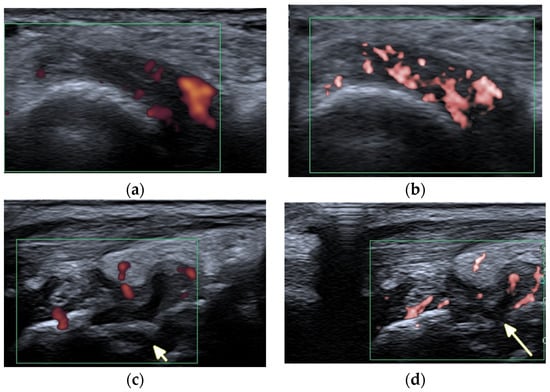

The imaging findings in US and MRI are nonspecific for many rheumatic diseases because synovitis, tenosynovitis, and BME can be seen in many of them, such as RA, juvenile idiopathic arthritis (JIA), PsA, and SLE []. In SLE, however, US and MRI improve understanding of the erosive disease and joint pathology [] (Figure 2 and Figure 5). These advanced imaging methods identify articular and periarticular abnormalities in the early disease phase with high sensitivity, allowing for a more appropriate and accurate management and follow-up [].

Figure 5.

A 57-year-old patient with systemic lupus erythematosus. (a) Short-axis power Doppler and (b) superb micro-vascular imaging (SMI) ultrasound (US) images of the distal radioulnar joint. (c) Long-axis power Doppler and (d) SMI US images at the dorsal aspect of the radiocarpal and midcarpal joints show joint effusions and hyperemia consistent with synovitis with more vessels seen with SMI (b,d). Note an intra-osseous cyst-like change (short arrow) and cortical erosion (long arrow in (d)) in the carpal bone related to rhupus syndrome.

A literature search conducted by Ceccarelli et al. [] in a number of databases on SLE imaging [] found reported synovitis in almost 60% of patients with SLE, and the presence of erosions with a frequency ranging from 2% to 87% []. As expected, 87% of rhupus patients showed US-detected erosions. Patients with rhupus not only had a greater number of erosions, but also larger erosions than those with JA or NDNE arthritis, with prevalent involvement of the MCP joints []. US appeared more sensitive than conventional radiography in detecting bone erosions in SLE, although, comparing it with CT, the overall reliability of US in detecting bone erosions was moderate for rhupus syndrome (0.55) and JA (0.58) and poor for NDNE arthritis (0.10) [].